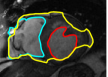

IV-A Tracking Multiple Regions

In cardiac image analysis, there are multiple structures (the right and left ventricles, and myocardium) that all useful and should be segmented. Our method is easily adaptable to this case. Indeed, computation of in Section III-C can be readily generalized. In general, multiple level sets should be used to represent multiple regions. However, in our case of interest (ventricles and surrounding epicardium), the regions form a rather simple topology (see Figure 3), and all regions can be represented using a single level set.